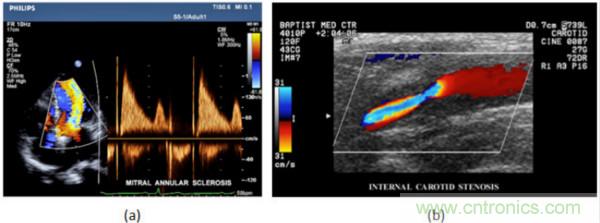

在CW和PW多普勒模式中,流信息是從一個聚焦聲束中獲得的,類似於A模式成像。在20世紀80年代,研究人員基於彩色多普勒技術完成了血流分布的二維信息可視化。彩色多普勒處理也是基於B模式/PW模式信號路徑。從感興趣區域收集多幀RF數據。由於感興趣區域中的血液流動導致圖像幀之間存在數據差異。相域中的自相關和時域中的互相關兩種算法可從RF數據中提取數據方差(即血流速度和方向信息):。根gen據ju預yu定ding義yi的de顏yan色se漸jian變bian條tiao相xiang應ying地di映ying射she包bao括kuo速su度du和he方fang向xiang的de血xue流liu信xin息xi。通tong常chang,藍lan色se和he紅hong色se代dai碼ma分fen別bie識shi別bie朝chao向xiang和he遠yuan離li換huan能neng器qi移yi動dong的de血xue流liu。當dang流liu速su增zeng加jia時shi使shi用yong更geng亮liang的de顏yan色se,反fan之zhi亦yi然ran。顏yan色se映ying射she的de2D分布始終疊加在Bmoshituxiangshang,yishishitongshixianshigetijiepoujiegouhexueliu。taduiyuzhenduanxinxueguanjibing,ruxueguanbisaihexinzangbanmofanliu,jiqiyouyong。dianxingdecaiseduopuletuxiangruxiatusuoshi,(b)顯示頸動脈狹窄引起的血流流速變化。

圖7.彩色多普勒成像:(a)以彩色多普勒和CW模式獲得的圖像(由Philips提供); (b)顯示頸動脈狹窄的彩色多普勒(由GE提供)